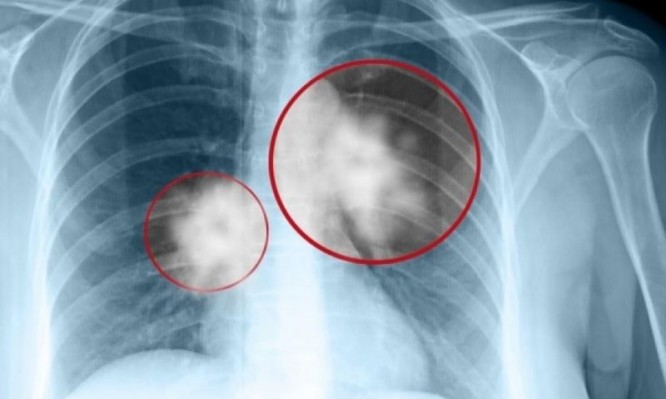

Νέα Θεραπεία για το μεταστατικό καρκίνο του πνεύμονα

Ο καρκίνος του πνεύμονα είναι η κύρια αιτία θανάτου από καρκίνο παγκοσμίως. Κάθε χρόνο πεθαίνουν 1,76 εκατομμύρια άνθρωποι εξαιτίας της νόσου. Αυτό μεταφράζεται σε περισσότερους από 4.800 θανάτους σε όλον τον κόσμο κάθε ημέρα. Ο καρκίνος του πνεύμονα μπορεί γενικά να διακριθεί σε δύο βασικούς τύπους: τον ΜΜΚΠ και τον μικροκυτταρικό καρκίνο του πνεύμονα. Ο ΜΜΚΠ είναι ο πιο συχνός τύπος, αντιπροσωπεύοντας περίπου το 85% όλων των περιπτώσεων. Ο ΜΜΚΠ περιλαμβάνει τον πλακώδη και μη πλακώδη καρκίνο του πνεύμονα. Η χρήση του συνδυασμού atezolizumab και bevacizumab μπορεί να συμβάλει στην ενίσχυση του ανοσοποιητικού συστήματος για την καταπολέμηση του προχωρημένου ΜΜΚΠ, ως θεραπεία πρώτης γραμμής. Το bevacizumab, εκτός από την τεκμηριωμένη αντι-αγγειογενετική δράση του, μπορεί να ενισχύσει περαιτέρω την ικανότητα του atezolizumab να επαναφέρει την αντικαρκινική ανοσία, αναστέλοντας τον υποδοχέα VEGF που σχετίζεται με την ανοσοκαταστολή, διευκολύνονταςτη διήθηση των Τ-κυττάρων στον όγκο και προάγοντας  την ενεργοποίηση των Τ-κυττάρων έναντι των καρκινικών αντιγόνων.